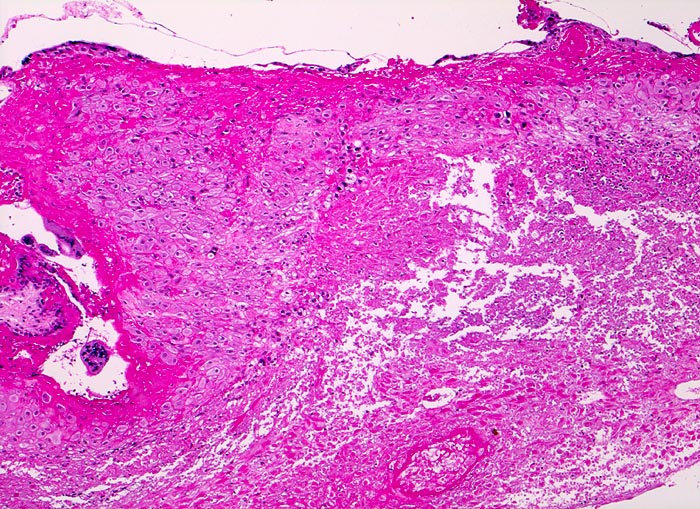

PathoPic ID 4676 - Abortkurettage: nekrotisches Deziudafragment

Abortkurettage: nekrotisches Deziudafragment

Nach längerer Retention zeigt die Dezidua eine ausgedehnte

granulozytär demarkierte Nekrose.

Synzytiotrophoblastäre Riesenzellen.

Missed abortion in der 11. Schwangerschaftswoche, sonographisch entsprechend der 9. Schwangerschaftswoche.

Ausgedehnte Nekrosen der Dezidua geben einen Hinweis auf ein länger zurückliegendes Abortgeschehen.